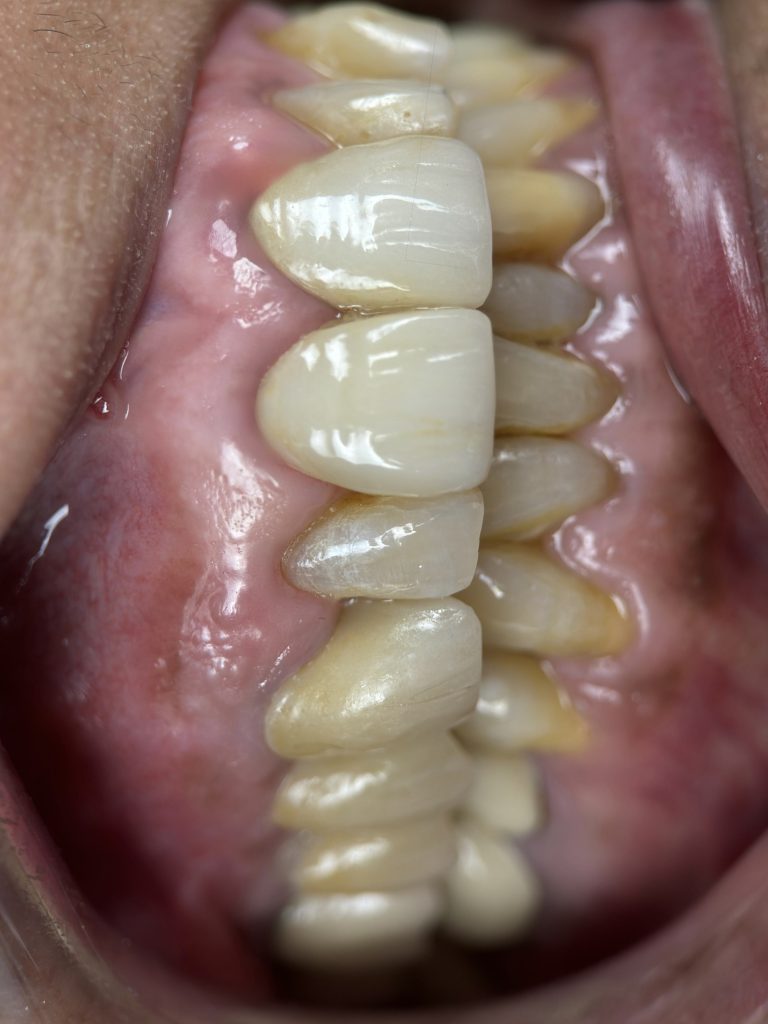

FIVE-YEAR FOLLOW-UP

At 5 years:

- Tooth structure remained intact

- Prosthetic margins were stable

- Periapical radiographic healing was evident

- Patient remained asymptomatic

- Excellent gingival response observed

- No secondary caries or debonding

- Occlusion stable and functional

✅ Long-term quadrant stability achieved